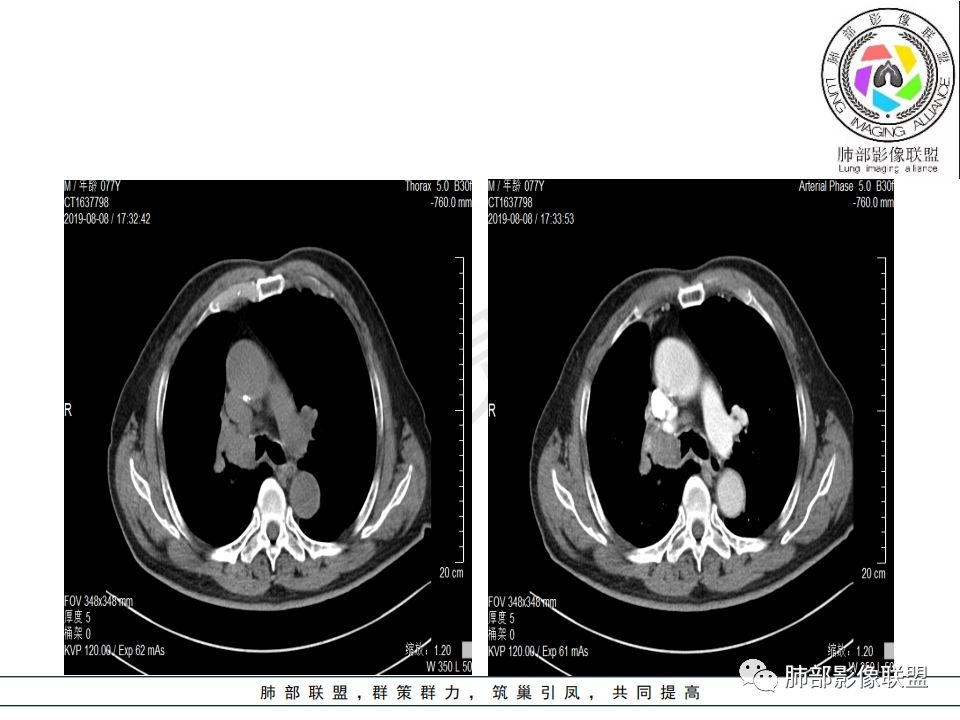

病史:男.77岁,咳嗽1月;干咳,少许白痰,无发热,2013胃癌术后,角蛋白24.65(0-3.07),SCC和proGRP不高;

影像:影像右侧大支气管阻塞,临床没有症状或很轻微,要想到胃腺癌转移;胸壁代偿好,透亮度稍低不明显,慢性过程;34.8-52.5HU,主病灶支气管前壁另有1结节,都做成增强两期了,动脉期较平扫有强化;

诊断:多发,转移,无淋巴结及胸腔积液;

鉴别:原发鳞癌。

又是一个支气管腔内占位,按常规,右肺上叶支气管占位,突入腔内,上叶不张,恶性没问题,鳞癌可能,但这么大,坏死少,是个疑点

从强化情况和冠状位看主要还是从外向内的一个肿块,有不张,但不张范围不大,近端支气管堵塞,考虑腺癌或类癌(原发或转移都可能),鉴别鳞癌。

病理结果:腺癌,考虑来源消化道

1.右肺上叶较大块影,密度不均,轻度强化并见低密度区,所属支气管截断并腔内突入,是符合肺鳞癌的影像学特征和生物学行为的。

2.胃癌常会首先胃旁淋巴结、腹主动脉淋巴结转移,肝脏血行转移,以及双肺多发转移,本例孤立右肺上叶病灶巨大,多有不符。

3.胃癌多血供,患者肺内病灶轻度强化。